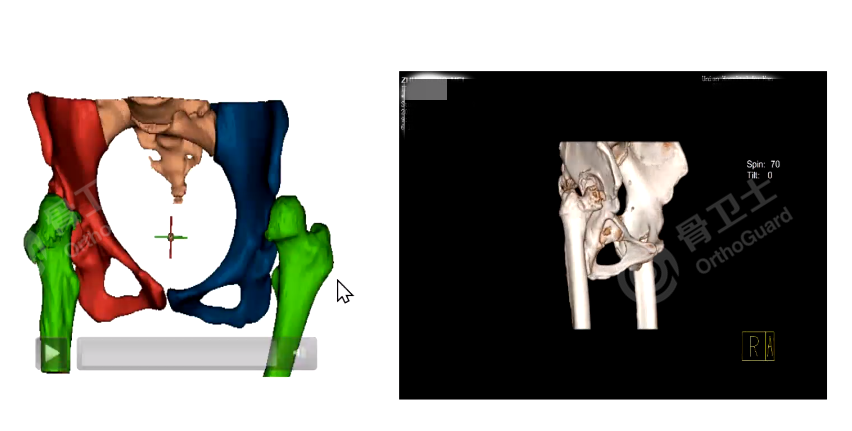

杨述华教授指出,术前应完善患者的三维CT,检查患者髋臼情况,做好计划,用模板法、测量法等方式计算,找到真臼的旋转中心,这对手术成功至关重要。如果能做3D打印,对手术也有很重要的参考价值。